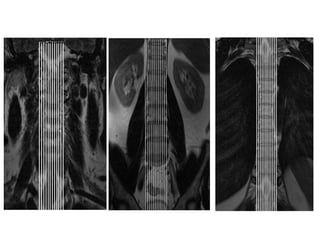

LOCALIZADOR

ROTINA

PLANEJAMENTO